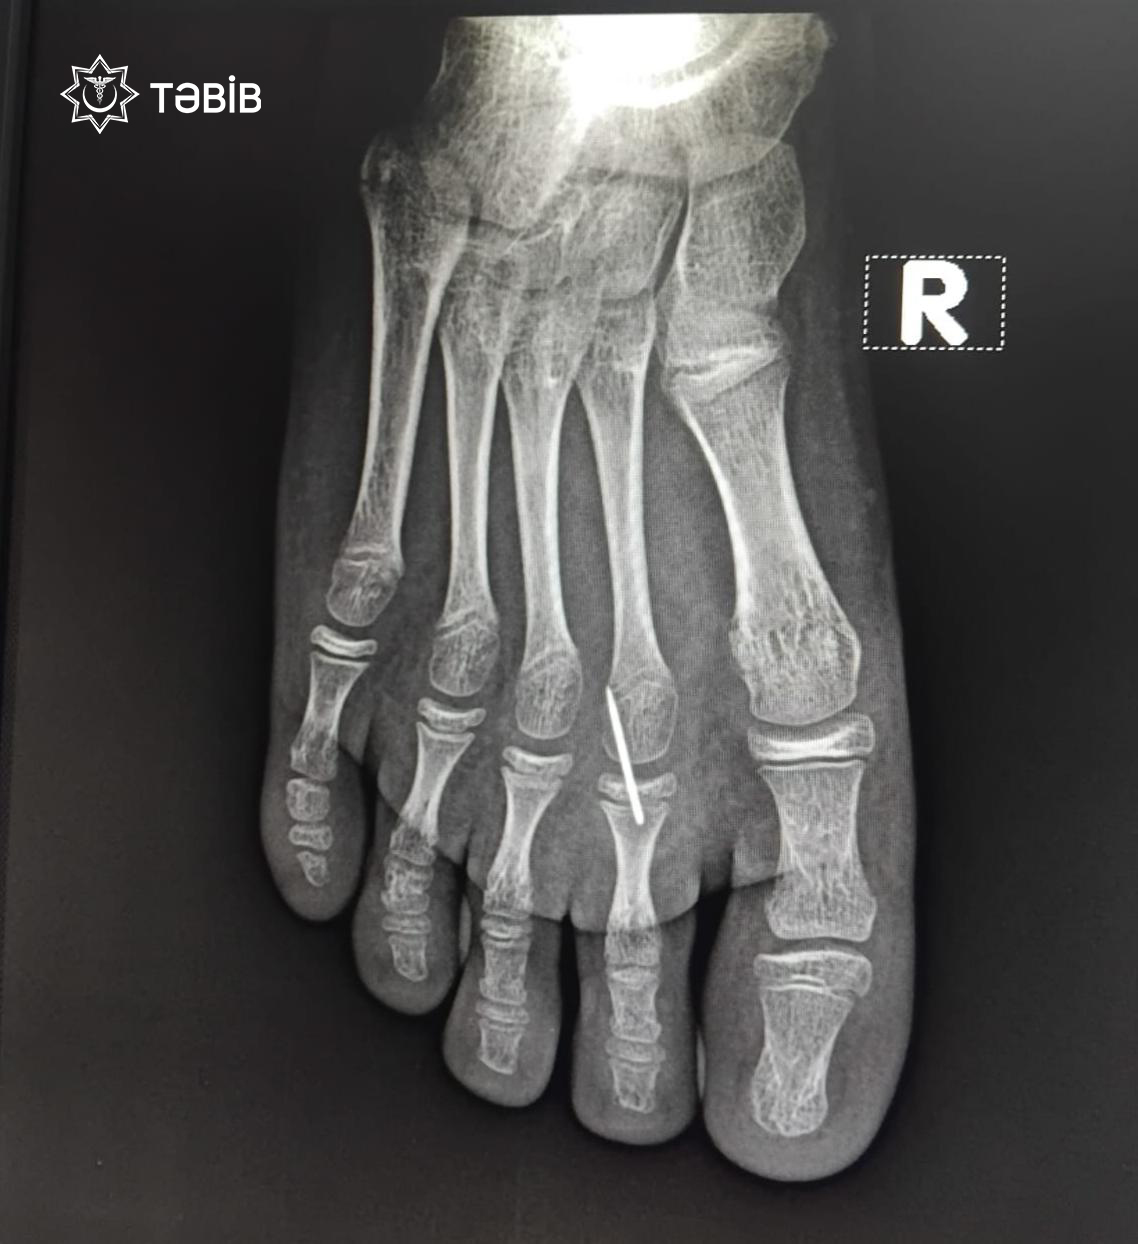

“Ayağında davamlı ağrı və şişkinlik şikayətləri ilə xəstəxanaya gətirilən 11 yaşlı uşağın rentgen müayinəsi zamanı sağ ayağının pəncə nahiyəsində yad cisim aşkarlanıb”.

“TƏBİB-in tabeliyində fəaliyyət göstərən Binəqədi Tibb Mərkəzində müayinədən keçən 2014-cü il təvəllüdlü uşaq (qadın cinsli) cərrahi əməliyyat olunub və pəncə nahiyəsindəki yad cisim – iynə parçası təhlükəsiz şəkildə xaric edilib.